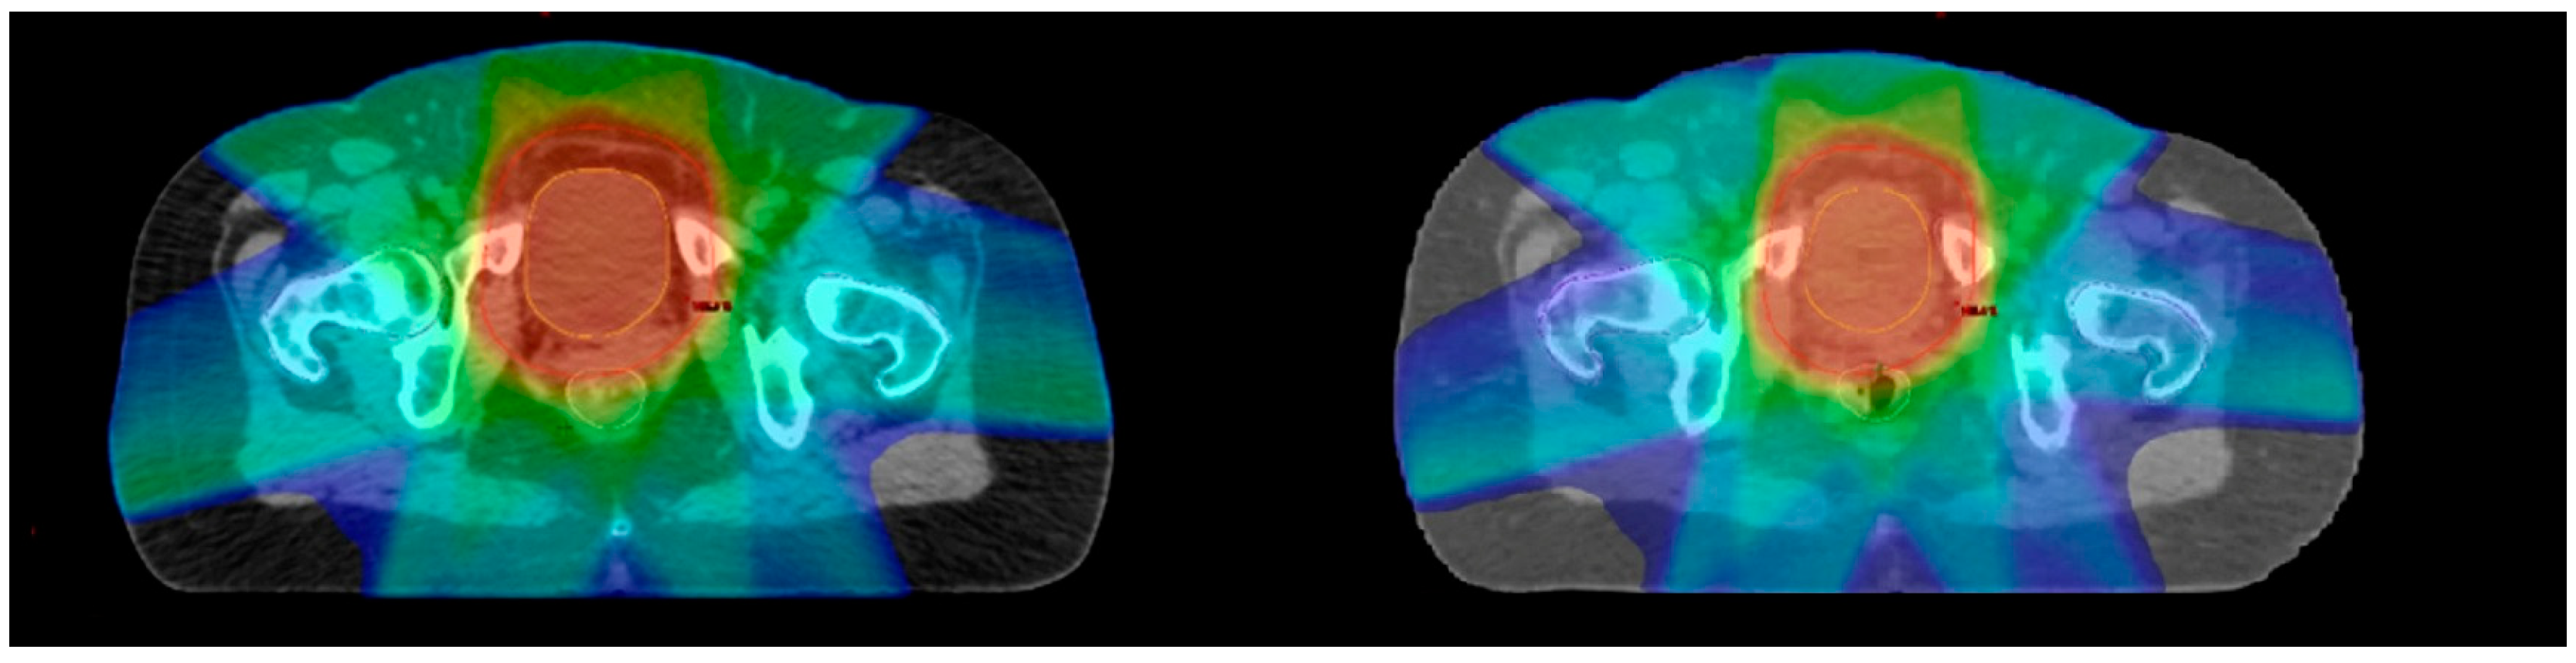

Each network training process took a mean of 24 h, while the mean generation time for a sCT study was 74 ± 7 s. The image selection process initially performed resulted in a discard of 3128 and a selection of 1379 paired images that met the image quality criteria. A learning rate of 2·10−4 and a lambda value of 2000 were identified as optimal hyperparameters set during network optimisation. Figure 1 reports a comparison between the sCT obtained using the optimal hyperparameter set and the corresponding CBCT and CT for a test patient chosen as an example.

Figure 1. Example of CT (left), CBCT (centre), and synthetic CT (right) generated in the axial, sagittal, and coronal planes in a pelvic case.